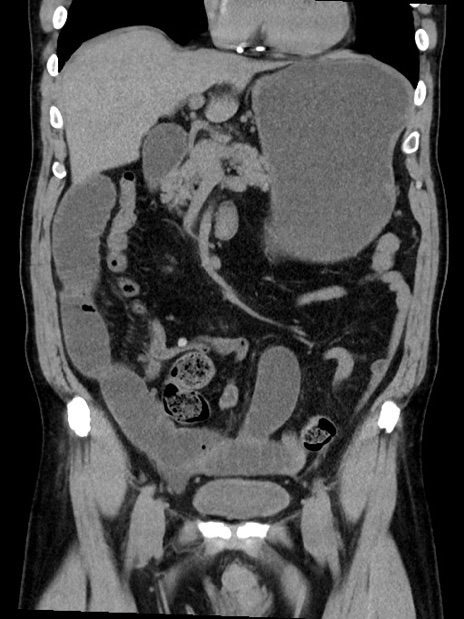

症例35(冠状断像)

【症例】70歳代 男性

【主訴】腹部膨満、嘔吐

【現病歴】昨日より腹部膨満感出現。本日増悪し、仙痛出現。嘔吐あり、受診。

【既往歴】糖尿病、胆摘後

【身体所見】BP 149/80mmHg、HR 74/min、BT 35.9℃、腹部:膨満、軟、圧痛なし。腸雑音減弱あり。上腹部正中切開瘢痕あり。

【データ】WBC 13500、CRP 1.72